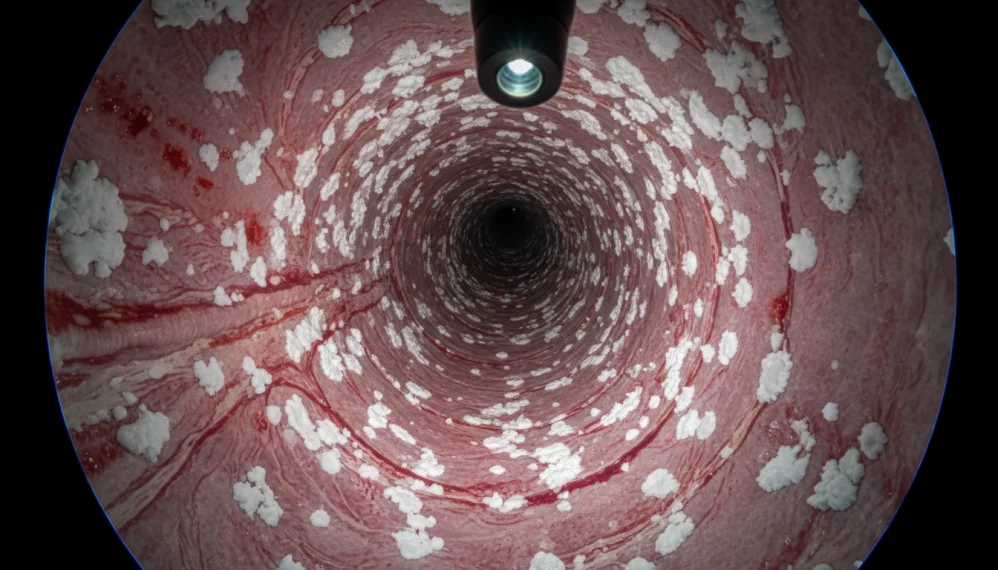

Rareori, candidoza esofagiana a fost asociata cu febra. In urma endoscopiei, la pacientii diagnosticati cu candidoza esofagiana se pot observa leziuni exudative albe, similare cu cele specifice candidozei bucale. Gradul de raspandire si contagiozitate al candidozei esofagiene difera de la un individ la altul.

Deoarece candida este o flora micotica normala in tractul bucal si gastrointestinal, izolarea candida din specimenele de sputa si scaun nu poate pune un diagnostic de infectie cu candida, care necesita adesea dovezi histopatologice. Caracteristicile patologice ale tesutului biopsiei endoscopice sunt multiple abcese cu reactie inflamatorie acuta. Neutrofilele sunt predominante, iar sporii fungici si pseudohifele sunt vizibile. Modul cel mai precis de a diagnostica aceasta conditie este prin intermediul analizei sau culturilor probelor recoltate. O alta metoda este endoscopia directa, cu ajutorul unui instrument (endoscop) care are la un capat o sursa luminoasa si o camera de luat vederi.

Instrumentul va fi introdus prin cavitatea bucala si prin esofag si se vor putea vizualiza pe un monitor imagini directe din interiorul esofagului. De asemenea, vor fi prelevate probe din interiorul esofagului pentru evaluare.